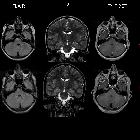

Four-year

follow-up study in a NF1 Boy with a focal pontine hamartoma. MRI (Flair, T2, and T1 sequences) performed in the child at the admission (2007) and four years later (2010). 2007: Hamartoma in the right pontine region and swallen aspect of the omolateral cortico-spinal tract. High signal intensity foci diffuse in the cerebellar emispheres (T2 hyperintensities). 2010: unmodified size of the pontine hamartoma and persistent bulge of the right cortico-spinal tract. Unchanged the UBOs lesions too.